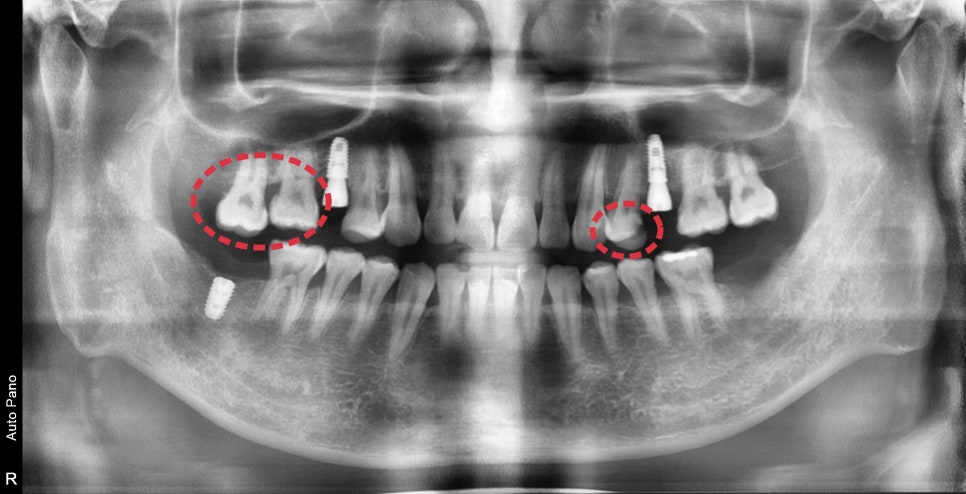

일단 가장 오래 걸리는 임플란트 먼저 수술을 했습니다.

아쉽게도 한 부위는 발치한지 얼마 안 되었기 때문에

바로 수술이 불가능하였고 추후에 뼈가 회복되고 진행하기로 했습니다.

표시된 부분은 신경치료가 진행되었습니다.

충치가 깊은 치아도 있었고 대합 치아의 부재로 인한

치아가 너무 많이 내려가 있어 신경치료+보철치료를 하지 않으면

치아의 높이를 맞출 수가 없었습니다.

신경치료는 여러 번 내원이 필요한 치료였기 때문에

보철치료까지 완성될 때쯤은 임플란트의 고정력이 좋아질 시기와 비슷하여

비슷한 시기에 보철치료까지 완성할 수 있었습니다.

신경치료와 보철치료가 완료될 때쯤

남아있던 한 부위 임플란트를 수술할 수 있었습니다.